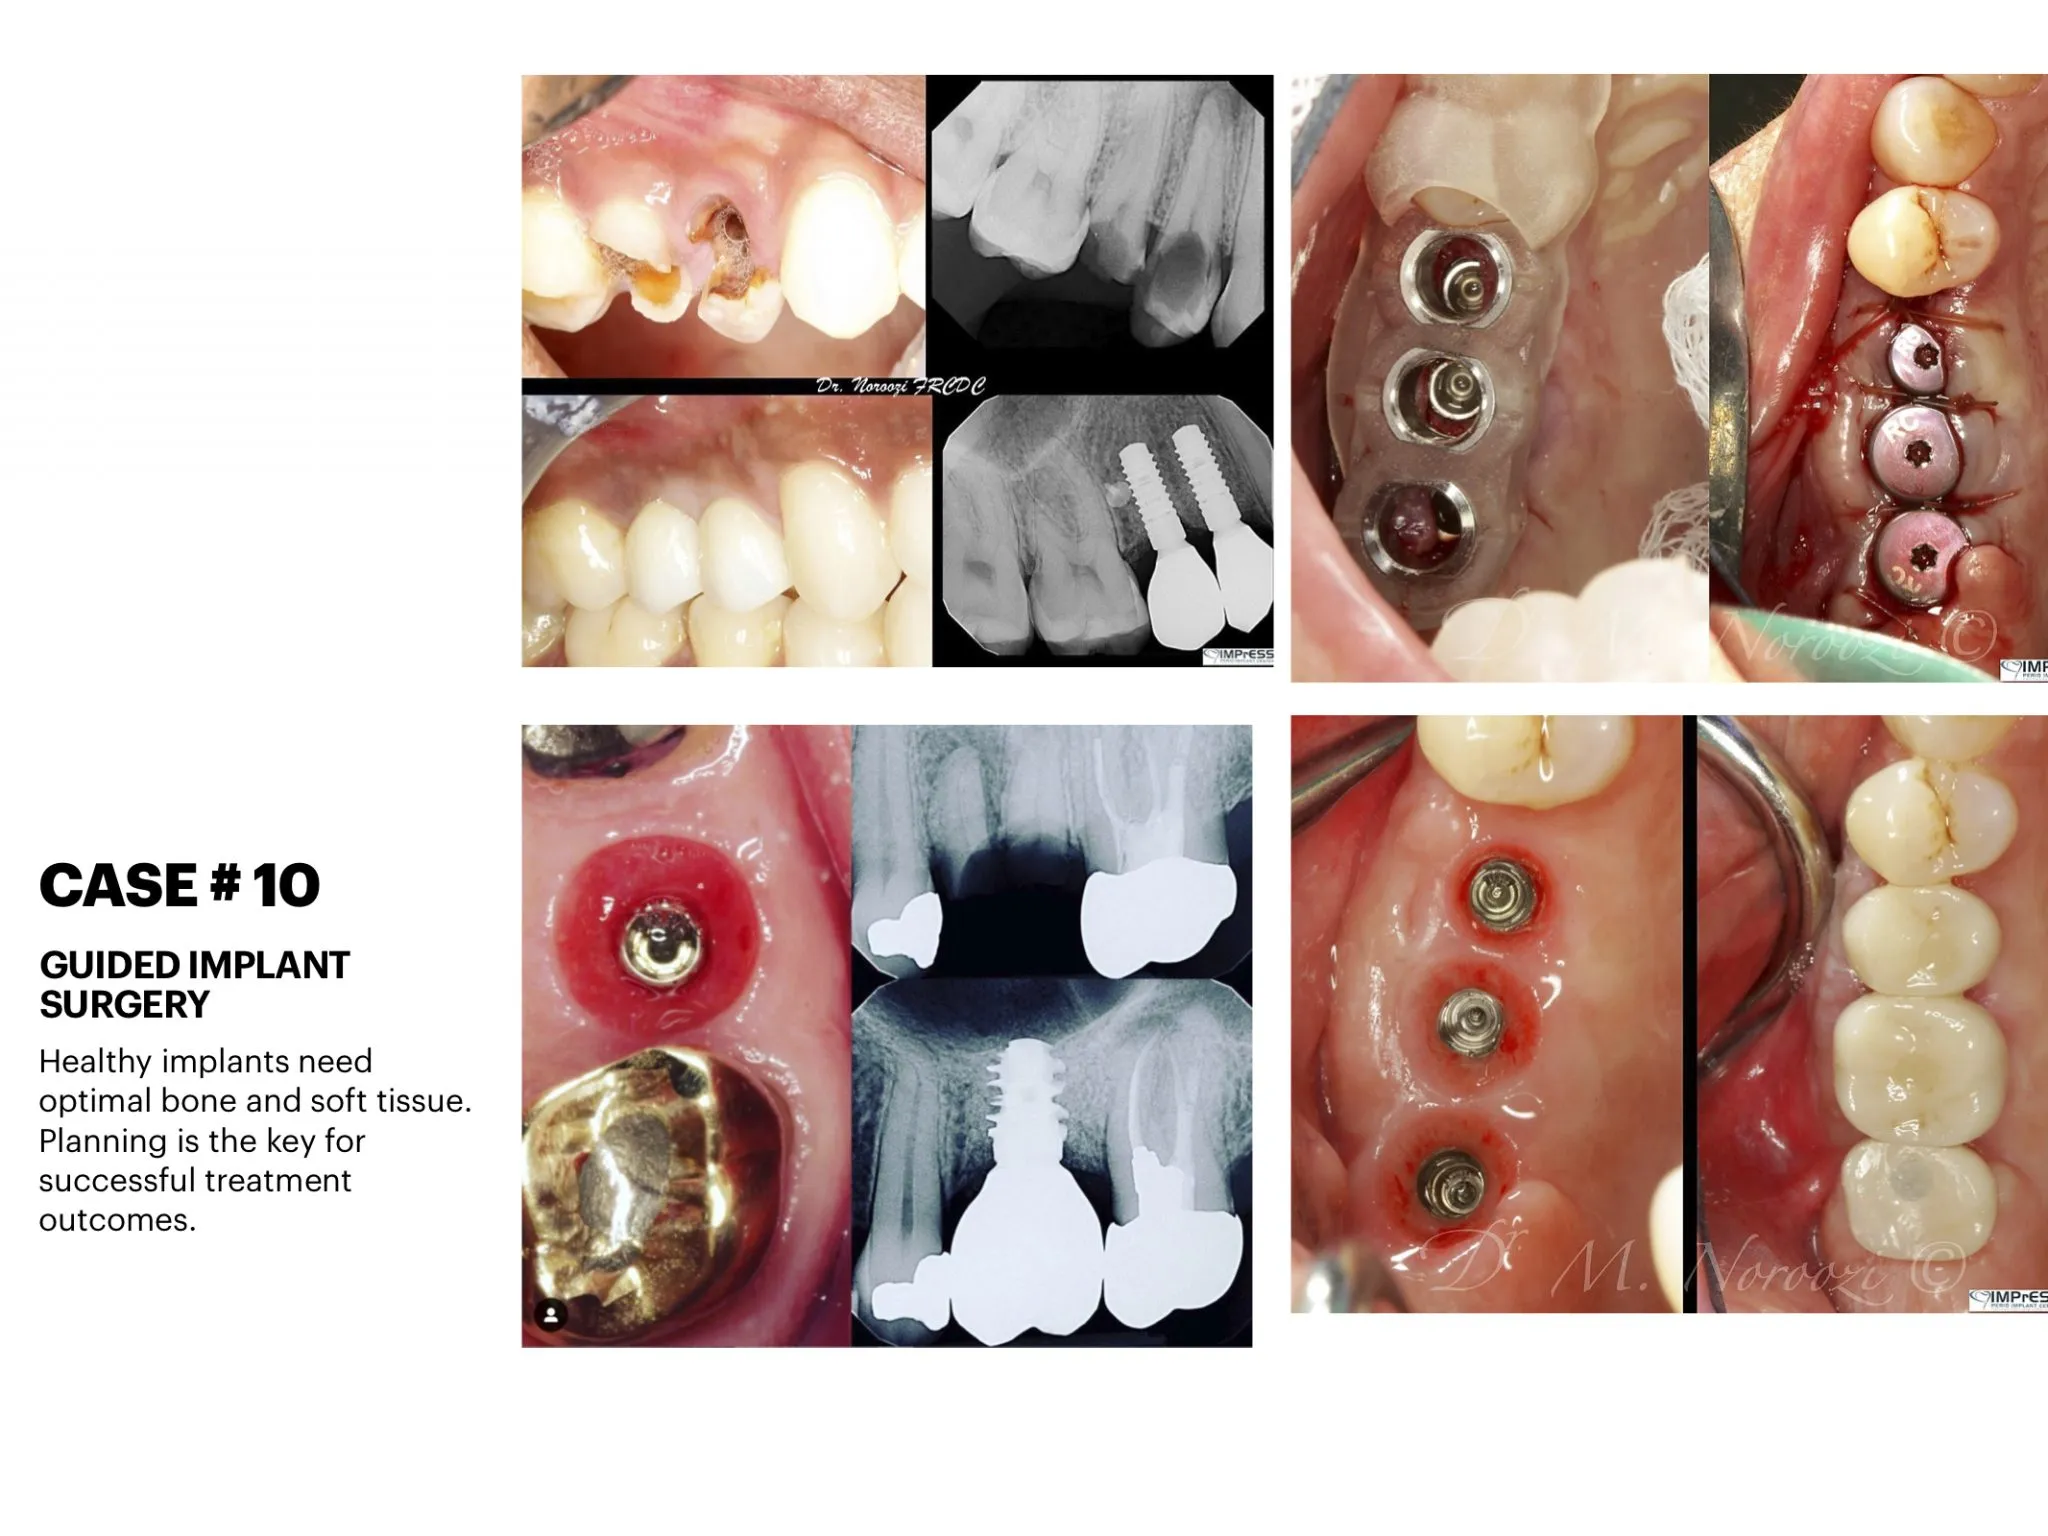

Dental implants are nothing new. They have been used to permanently replace teeth since the mid-60s. Dental implants have many advantages compared to traditional crown and bridge solutions. If one or more of your teeth are missing, there are a number of ways to replace them. An alternative to bridges, partials, or complete dentures may be dental implants. Implants are used to replace missing roots and support artificial replacement teeth. They are comfortable and look like natural teeth. Computer Guided Dental Implant Surgery

We use digital innovations to digitally plan implant placement to receive the most predictable outcome through:

• Create radiographic and surgical templates from guided surgery software

• Nerve detection, segmentation, and implant placement for prosthetic-driven implant planning with guided surgery software.

• Precision surgical guided placement using restorative-driven three-dimensional imaging and planning allows for more predictable surgical placement.

• High surface digital impression scanning and CAD/ CAM milling allows for precision design and modeling for improved accuracy of both the abutment and restorations. Combining these digital technologies allows us to plan and treat the patient in a more efficient manner with more predictable results.

General Disclaimer: The results in the photographs are examples only and do not imply any certainty of the result of a procedure, and all outcomes are subject to the circumstances of the individual patient.